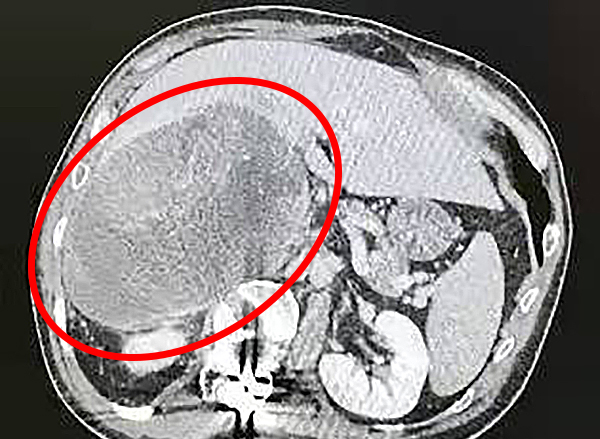

經檢查,張先生不但患有腹膜后巨大腫瘤以及嚴重凝血功能障礙,同時還有嚴重脊柱側彎畸形的病史,影像學提示:腫瘤直徑約17厘米,且腫瘤位置極深,術中無法獲得良好的視野暴露,因此手術難度及風險非常大。

專家經過研究討論后認為,張先生的治療有三大難點:首先,患者腹膜后腫瘤來源于腎上腺的可能性比較大,傾向惡性腫瘤,腫瘤還向四周擠壓,并與肝臟、腎臟、腎動靜脈、腔靜脈等重要器官和血管關系密切,腫瘤切除難度大;其次,患者腫瘤巨大,被肝臟完全包裹,并且由于脊柱側彎胸廓前傾,導致腫瘤位置較深,術中無法獲得良好的視野暴露;最重要的是,由于患者合并有嚴重的凝血功能障礙,考慮凝血VII因子缺乏,該疾病極為罕見,術中、術后可能會出現無法挽救的大出血,對患者生命造成極大威脅,這就需要血液內科、麻醉科、檢驗科等多學科的通力配合。